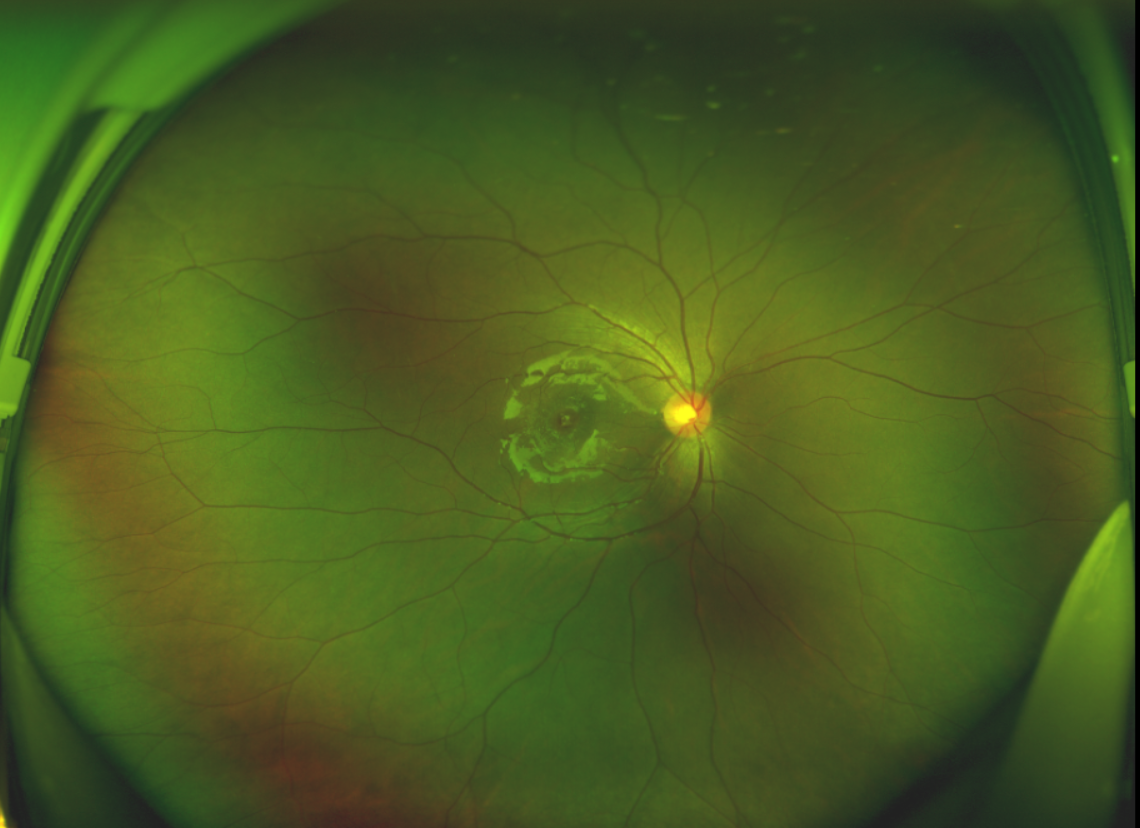

除此之外,利用自體組織覆蓋為黃斑裂孔提供了理想的愈合環(huán)境,裂孔閉合速度顯著快于傳統(tǒng)方法。誠誠接受手術(shù)24小時(shí)后,檢查可見內(nèi)界膜瓣位置良好;術(shù)后1個(gè)月,黃斑裂孔已經(jīng)閉合,視力恢復(fù)到0.5;術(shù)后兩個(gè)月,視力進(jìn)一步提升到0.7。

黃斑裂孔

術(shù)后2個(gè)月 △